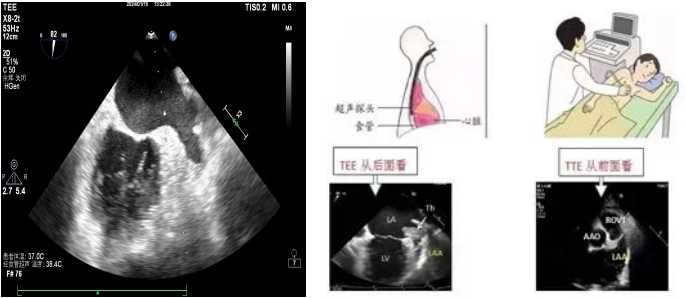

左心耳位于左心房的偏后上部分,大部分情況下被左心房主體部分遮擋,常規(guī)的經(jīng)胸超聲心動圖(TTE)很難清晰顯示。TEE是超聲探頭置入食道內(nèi),從心臟的后方進(jìn)行檢查,縮短了超聲探頭與心臟及距離,避免了肺氣干擾、肋骨遮擋等弊端,可直觀的從左心房看到左心耳,排查左心耳內(nèi)有無血栓。目前我院開展了常規(guī)經(jīng)食道超聲心動圖和無痛經(jīng)食道超聲心動圖檢查。